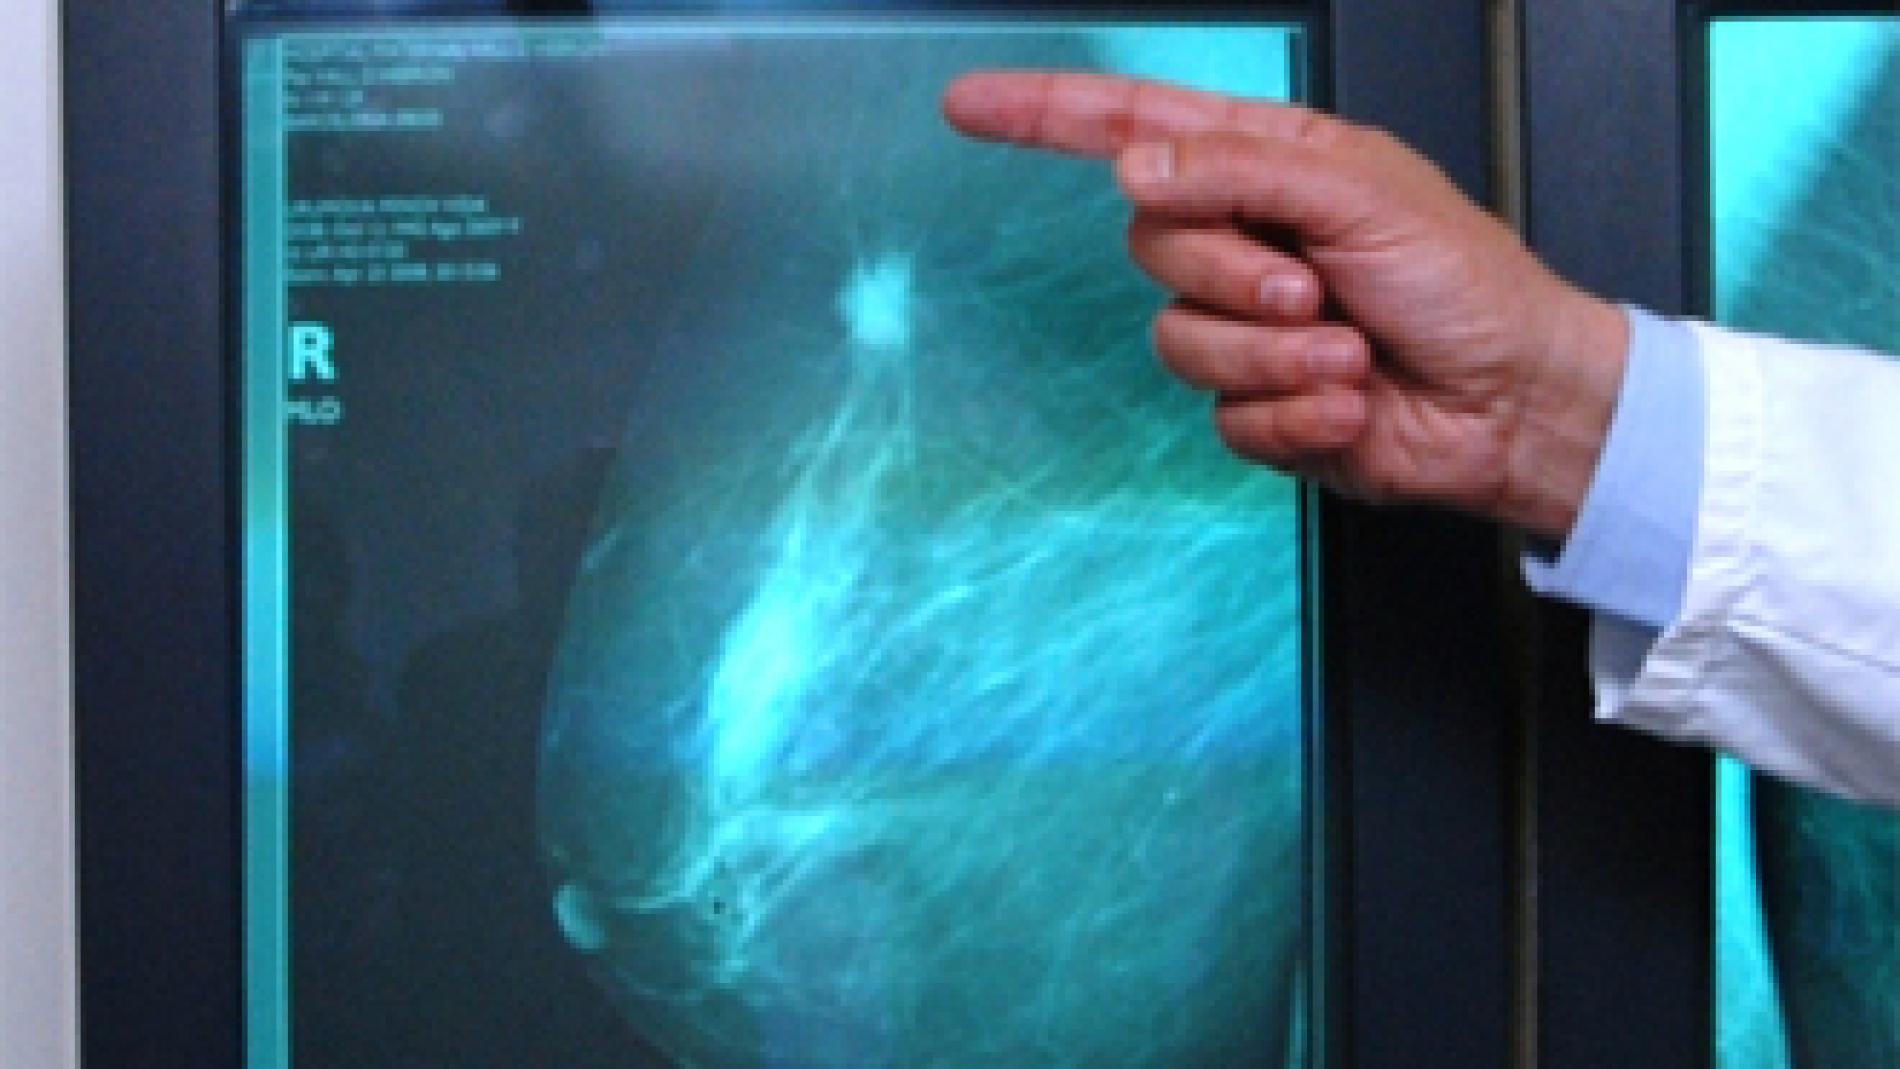

Vall d'Hebron successfully treats pregnant women with breast cancer

October 19, Breast Cancer World Day

The diagnosis of breast cancer during pregnancy presents various complexities for patients and practitioners since the benefit of the woman’s treatment must be compatible with the well-being of the foetus. Cancer diagnosed during pregnancy is rare, occurring in 2.3 cases out of every 100,000, however, this figure has progressively grown over recent years as women are becoming mothers at an increasingly older age. Twenty years ago therefore, the number of women that became pregnant at the age of 35 accounted for 35%, while today in Spain it is the average age that women have their first child. In 2006, a protocol was established at the Breast Cancer Unit, the Vall d’Hebron University Hospital, to treat women in a holistic manner involving a multidisciplinary team comprising gynaecologists, obstetricians, foetal medicine specialists, oncologists, specialized surgeons in breast cancer, and paediatricians. This integrated approach facilitates communication between the experts involved in decision-making as well as enhances the safety, flexibility and effectiveness of the management of these pregnant patients during treatment. The ultimate goal of this task force is to ensure the utmost safety and effectiveness for the mother without harming the development of the foetus. Patients that have been diagnosed with breast cancer during pregnancy have the option of either interruption or continuation of the pregnancy. Until now, many women have previously chosen the former because they were not offered an alternative. At the Vall d’Hebron University Hospital however, since this protocol was established, women are duly informed about the possibility of continuing the pregnancy and receiving the most appropriate treatment at the same time. Importantly, these patients require highly comprehensive monitoring starting at diagnosis, at which point the multidisciplinary team defines the best strategy to follow considering the stage of pregnancy and as well as that of the tumour. In accordance with this, a decision is made regarding initiating treatment with chemotherapy or surgery and timelines for treatment are established to achieve the maximum effectiveness for the mother and the safest treatment for the foetus. Thereafter, a circuit is established whereby each time the patient is to receive chemotherapy, a prior analysis and ultrasound of the foetus are carried out in addition to a check-up with the obstetrician and the oncologist to ensure the proper development of the foetus. The patient may then receive chemotherapy that same day. This monitoring is essential to control the development of the patient’s cancer and that of the pregnancy at all times. The key to the success of this programme is team-work as well as experience accumulated over the years in addressing the challenge of treating breast cancer during pregnancy. Furthermore, over recent years, advances have been successfully integrated into the treatment of these patients such as selective sentinel lymph node biopsy, taxane-based chemotherapy and foetal echocardiography, among others, which have led to comparable results to patients that are not pregnant, without harming the foetus. The experience accumulated in this field has also allowed the medical team responsible for this protocol to develop research projects aimed at improved outcomes for patients. Research focuses on the various effects chemotherapy may have on the foetus. In addition, the Vall d’Hebron Hospital collaborates with international groups also working on cancer and pregnancy to continue to improve protocols. At Vall d´Hebron the patient is centered at the core of all research programs from the translational and preclinical levels to the clinic. Our research consequently aims at discovering the factors and mechanisms driving tumoral progression to obtain more accurate prognosis, tailored diagnosis and ultimately personalized treatment for breast cancer patients. "This is facilitated not only through direct access to patients and tumor samples but also through the planned connectivity between basic, translational researchers and clinicians working as teams implicated in the various research projects, " explains Dr. Joaquín Arribas, Director of Preclinical Research at the Vall d´Hebron Institute of Oncology (VHIO). The type of research conducted al Vall d’Hebron can be exemplified by the case of HER2-positive breast cancers for, accounting for between 15 - 20% of all cases. Much progress in combating this tumor type has been made thanks to drugs directed against HER2 such as trastuzumab, pertuzumab, lapatinib, or T-DM1. Despite the undeniable success of these therapies, sadly, many tumors ultimately develop resistance against them. Groups at Vall d’Hebron are currently tackling this problem to optimize these therapies. To solve these remaining questions behind such resistance and given the immense challenges arising from cancer heterogeneity, research at Vall d´Hebron is basic-applied, adopting a purely translational approach. At molecular level, thanks to the development of xenograft models with explant tumors from patients in mice in order to mimic the patient´s disease and study tumor development in optimized research models, the detection of mutations and mechanisms of resistance to current therapies associated with the disease is both facilitated and accelerated.